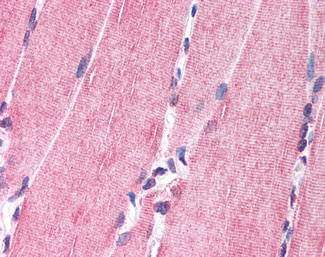

Anti-NRG1 antibody APR02149G IHC of human skeletal muscle. |